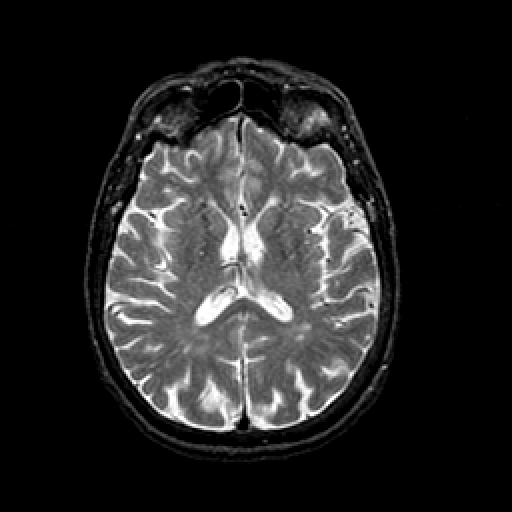

T2-weighted structural MR: Slice 30

Slice 30